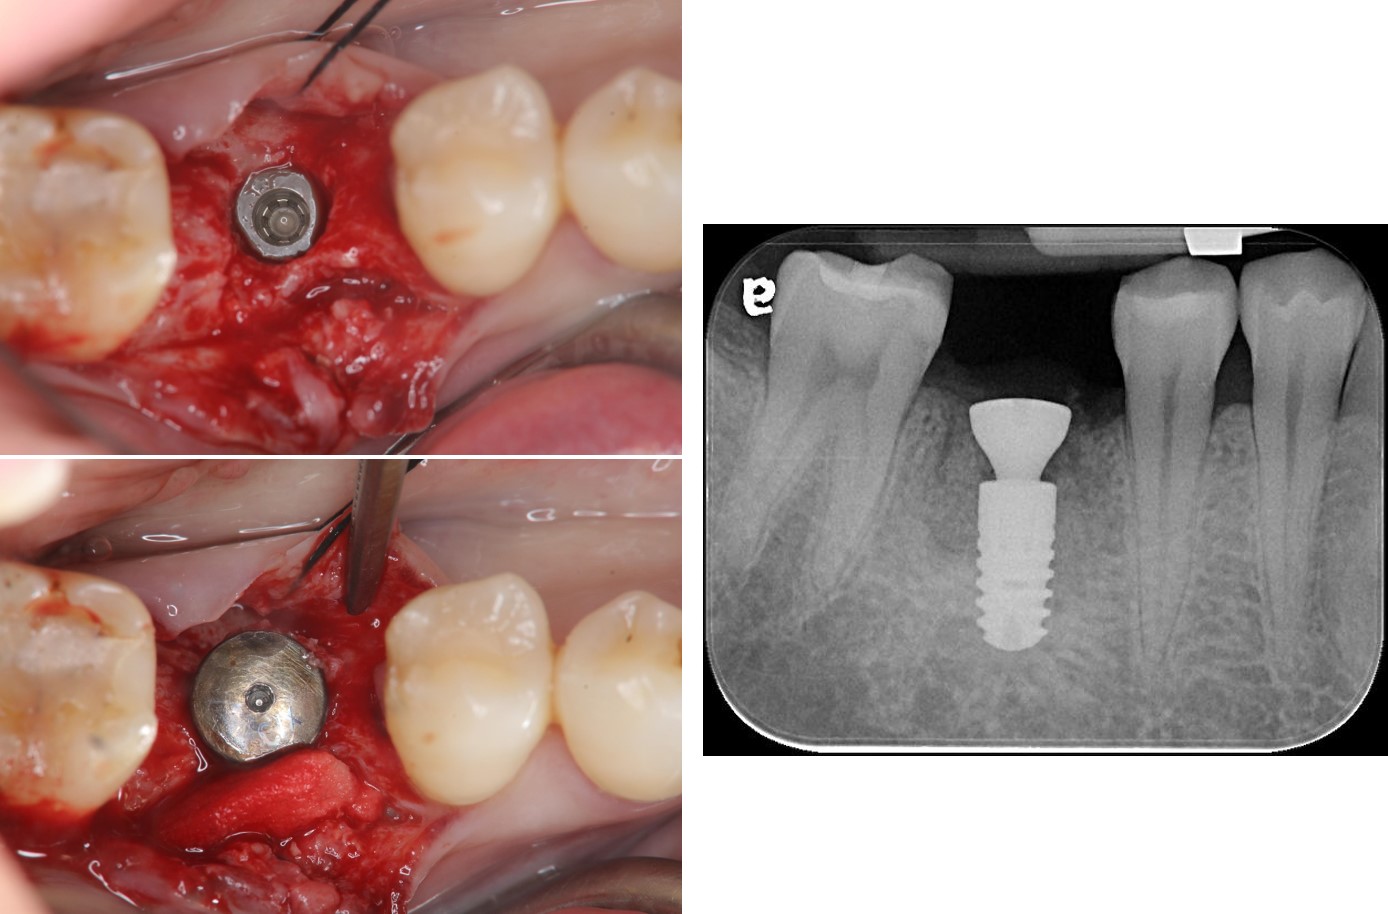

拔牙同時補骨

6個月後,骨癒合

植牙規畫模擬

植牙、補骨及補皮

植牙後,角度良好